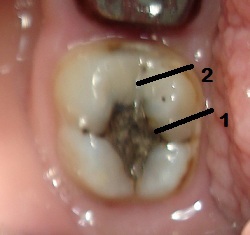

Пример 1.

Это исходная ситуация перед началом работы с данным зубом.

На вид зуб целый, пусть Вас не смущает цвет пломбы -1 - это амальгама (Вам известна она под названием -серебряная пломба), 2-пломба из композитного материала.